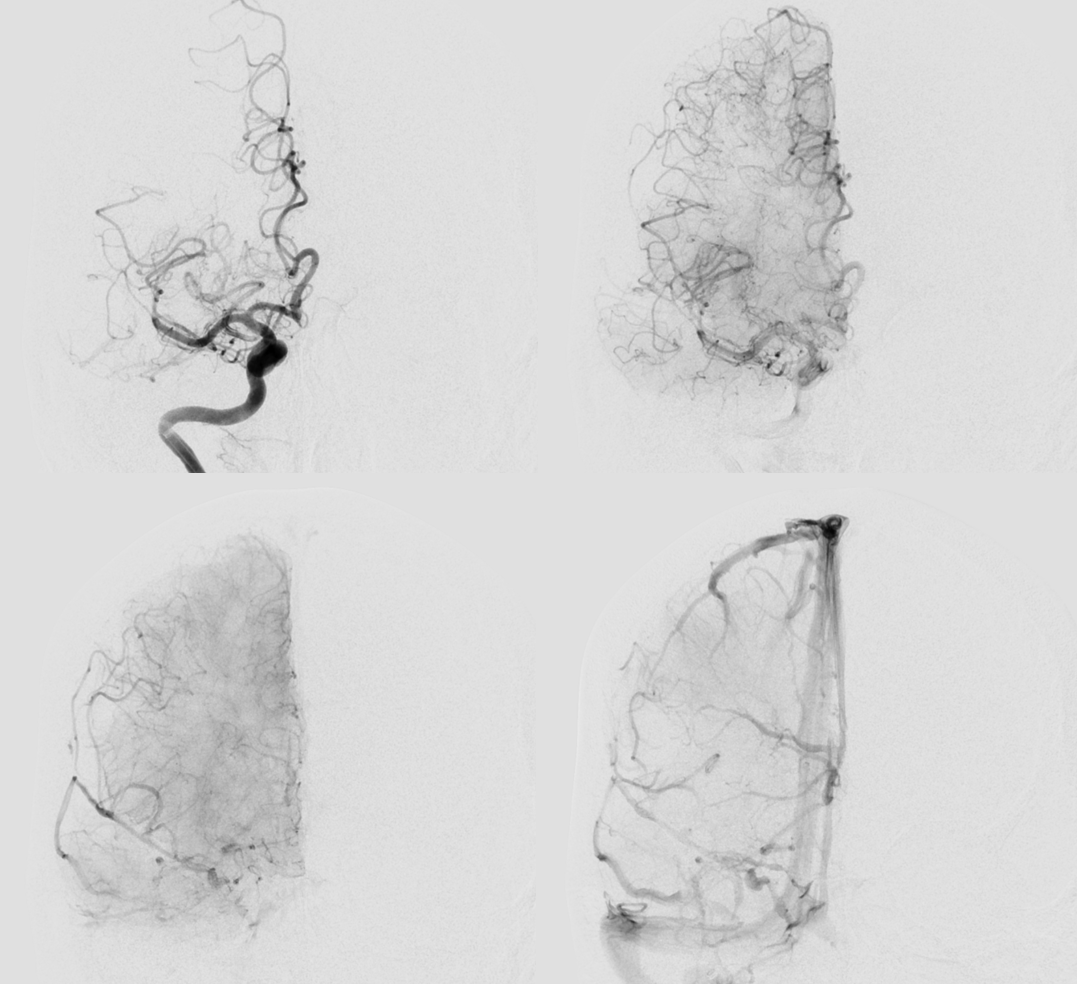

Angio

The proximal M2 occlusion is clearly visible

Thrombectomy

As predicted there is a second occlusion. See correlation between angios and DYNA